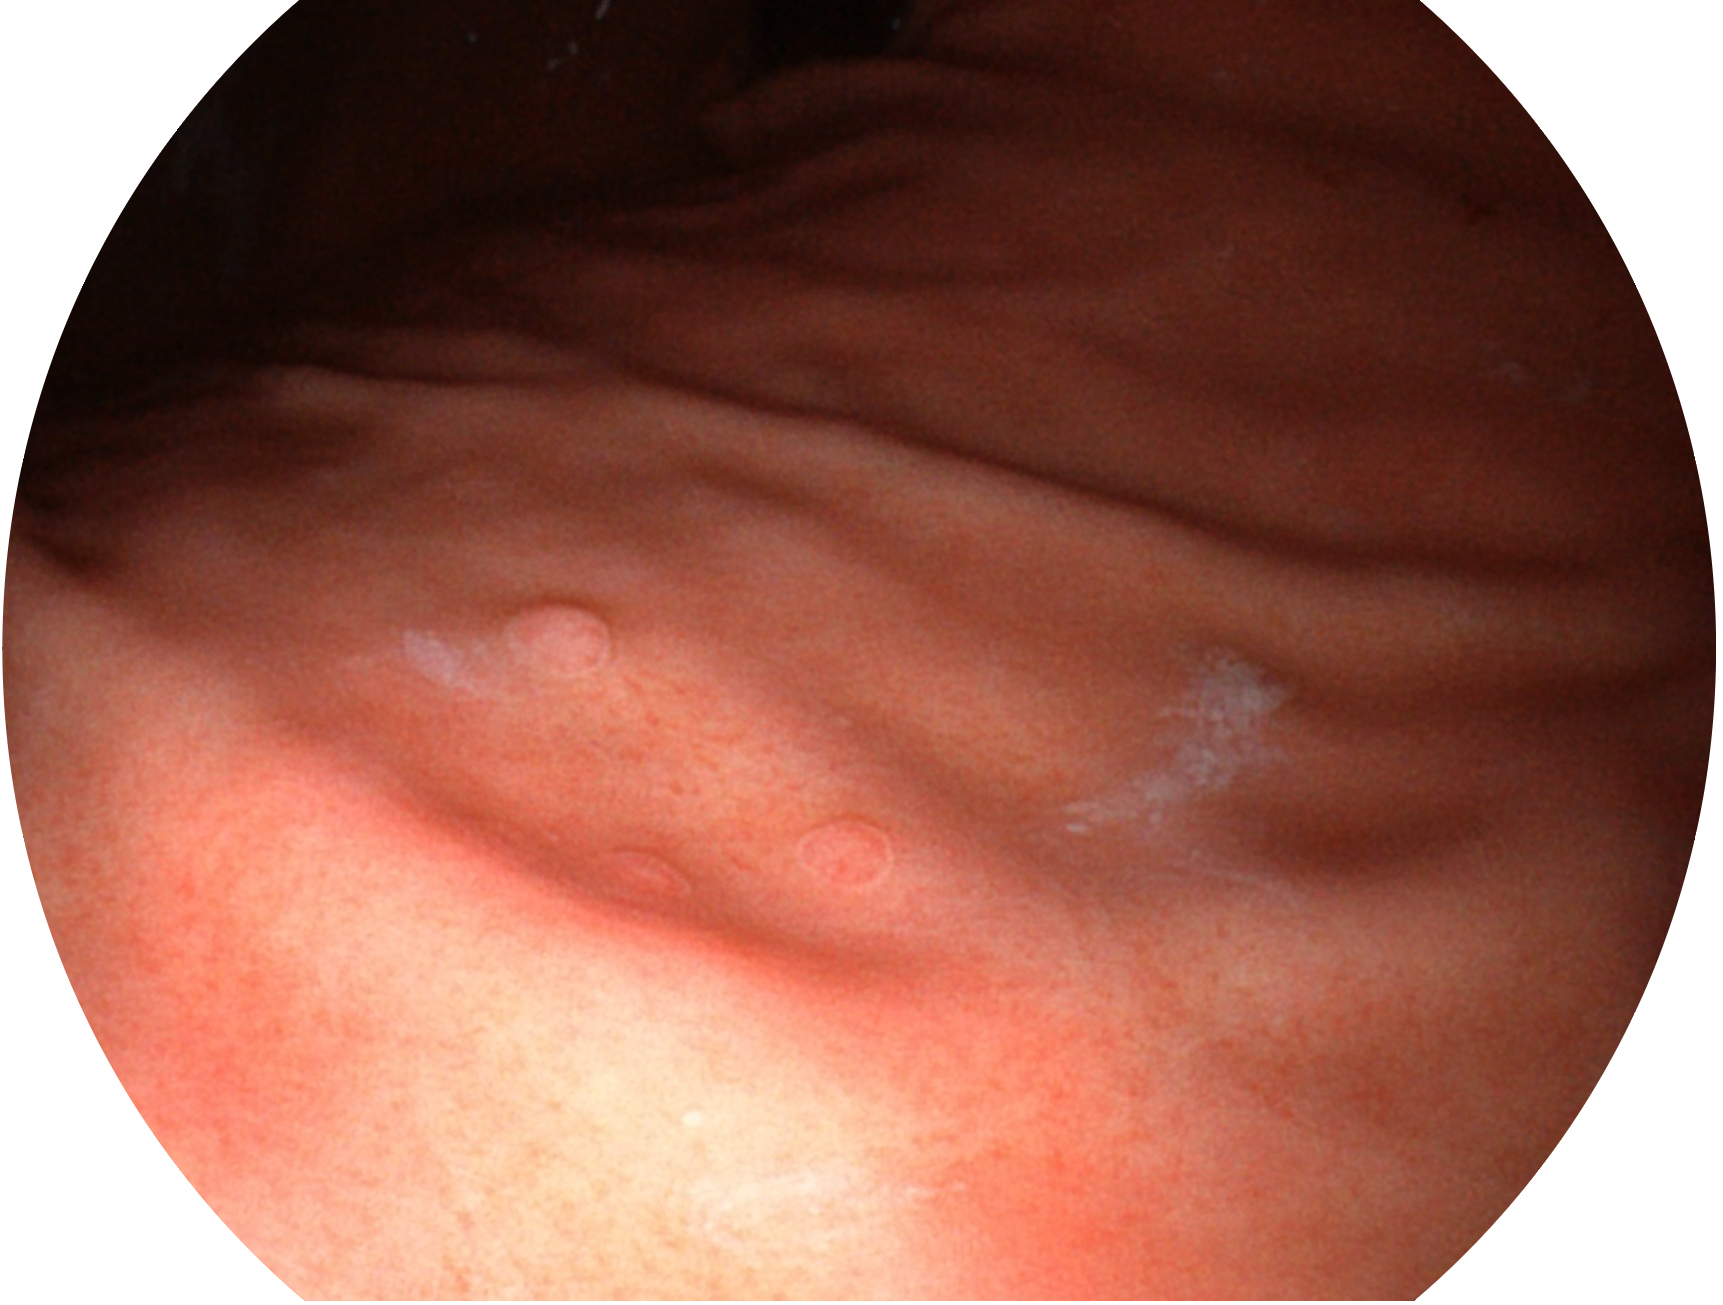

16877太阳集团新开发的内镜染色技术,主要是基于多波长LED 光源的开发,VLS-55Q 四波长LED 光源是由四个不同颜色的LED光按照相应照明模式所规定的特定发光比例进行合束后形成,合束后形成的照明光的光谱由红光、绿光、蓝光及蓝紫光这四个不同的波段范围构成。具有更高光谱自由度,通过光谱比例的控制,实现了聚谱成像技术,英文全称为“Spectral Focused Imaging, SFI”,缩写为“SFI”和光电复合染色成像技术,英文全称为“Versatile Intelligent Staining Technology, VIST”,缩写为“VIST”。